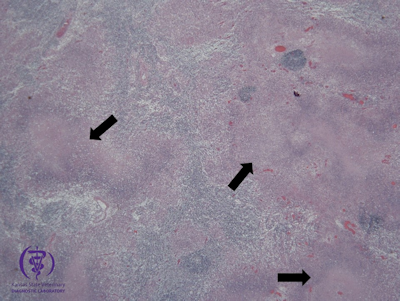

Figure 3. Histologic section of the spleen. H-E (2x).

Diagnostics: At necropsy approximately 50 percent of the spleen and liver contained multifocal, 1 mm diameter, well demarcated, round, tan nodules. Figures 1 and 2. No other significant gross lesions were found. Histologically, abruptly disrupting the parenchyma of the spleen and liver, there were multifocal, scattered areas of necrosis affecting both white and red pulp. Figure 3.